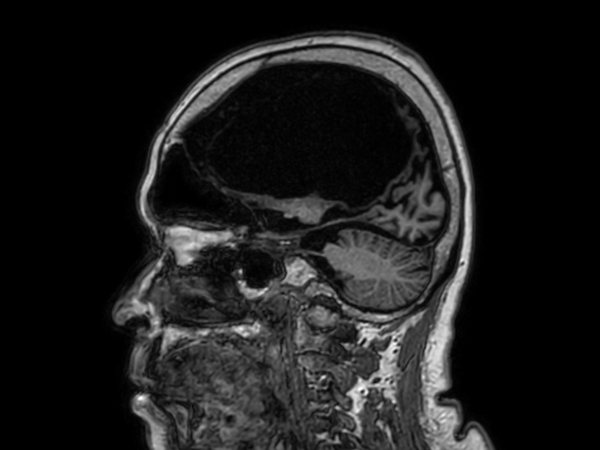

Sagittal 3D BrainVIEW FLAIR (without Compressed SENSE)